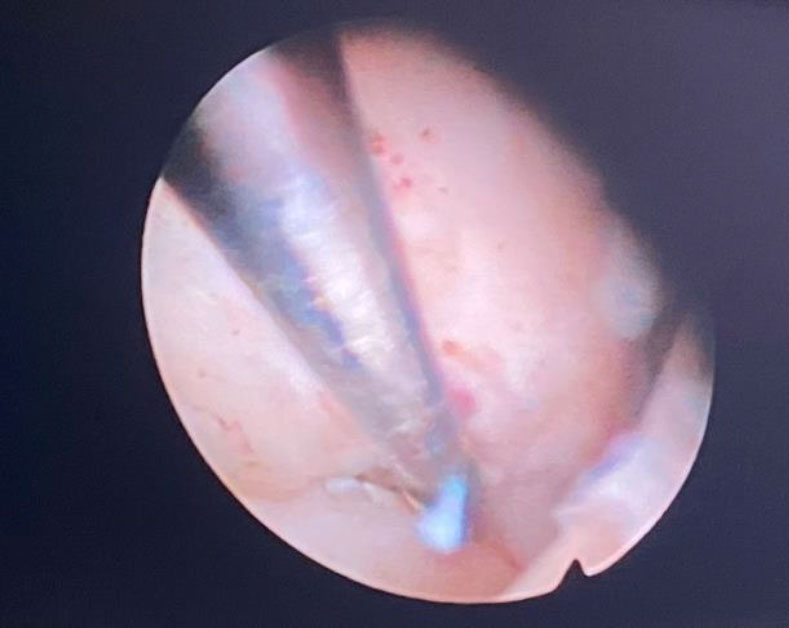

Figure 3. Myoma separation process from its bed

Patient was brought under general anesthesia. Hysteroscopy was performed and two submucosal myomas were identified in the lateral and posterior surface of the uterine cavity with a protruding dome with regular surface hysteroscopic grading type G1 for both of myomata. The myometrial free margin was identified, a bipolar loop and hysteroscopic scissors were used to enucleate the myomas.